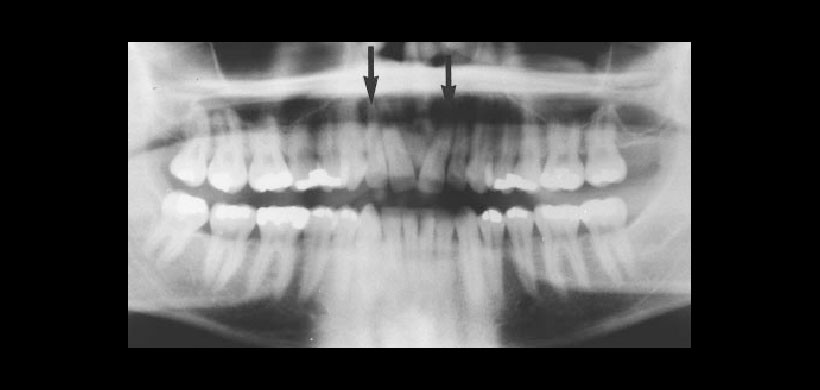

Radiográficamente, condrosarcoma presenta como una imagen radiolúcida de forma irregular, mal definidas con áreas dispersas al azar. La lesión puede aparecer lobulada y puede elevar el periostio adyacente para producir el aspecto de “rayos de sol”.

Fig 1. Radiografía panorámica de un hombre de 29 años de edad, con un aumento de volumen en la región anterior del maxilar, se observa una imagen radiolúcida de limites pocos definidos que ocasiona la divergencia de las raíces de los incisivos centrales superiores(flechas),